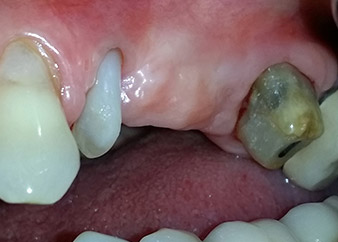

58-годишна пациентка се оплаква от болка и повишена подвижност в нейния мост върху зъб 24 с функция на абатмънт. На лице е периодонтално възпаление с дълбочина на джоба 7 mm мезиобукално и повече от 12 mm дистално, както и включена 3 градусова фуркация. Освен това, рентгенографията показва обширна периодонтална лезия около апикалната зона на (друго място) предварително ендодонтски обработен зъб 24 (Фиг. 1).

След един месец, в деня на операцията, болката и възпалението в зъб 24 е минимално, но подвижността в Miller class 2 е на лице. След отваряне на ламбата и почистването на периапикалната и перирадикуларната тъкани, обхватът на костния дефект стана очевиден (Фиг. 2 и 3).

В букалния корен, цялата вестибуларна и дистална кост липсва. Захващането е значително ограничено до палатиналния корен, подчертавайки предварително лошата прогноза. Зъб 27 също откри намалено хоризонтално захващане и минимално апикално разреждане (Фиг. 1) без клинични симптоми.